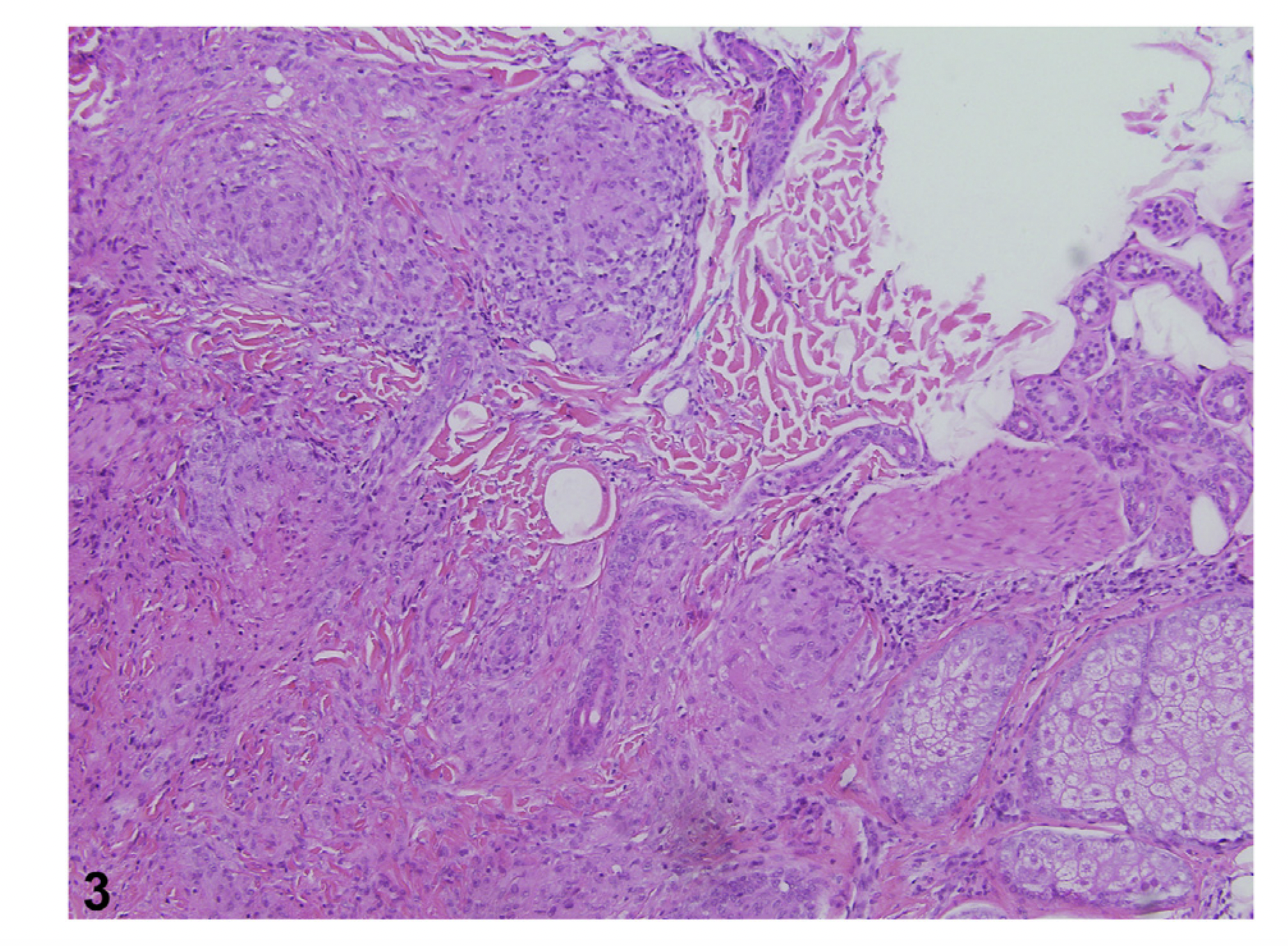

Histology from scalp in patient with sarcoidosis. Image from Barker C et al. Scarring alopecia and scalp pruritus. JAAD Case Rep. 2022 Nov 2;30:134-136. doi: 10.1016/j.jdcr.2022.10.021. eCollection 2022 Dec. Image used with creative commons license.

Histology from scalp in patient with sarcoidosis showing non caseating granulomas typical of the disease. Image from Barker C et al. Scarring alopecia and scalp pruritus. JAAD Case Rep. 2022 Nov 2;30:134-136. doi: 10.1016/j.jdcr.2022.10.021. eCollection 2022 Dec. Image used with creative commons license.